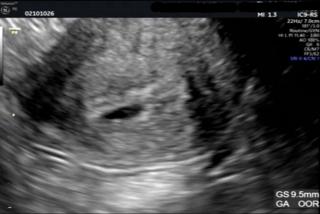

サイズは9.5mm

胎嚢の中に小さな卵黄囊も見えました!次は1週間後に心拍確認です♪